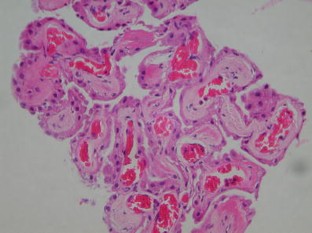

Cerebellopontine angle arachnoid cyst containing ectopic choroid plexus—case report

We present a rare and interesting case of a cerebellopontine angle cyst containing ectopic choroid plexus tissue in a 26 year-old female. Surgical resection was performed, and histological examination confirmed the presence of choroid plexus in the cyst wall. This is the first reported case of ectopic choroid plexus at the cerebellopontine angle in an adult. We present the case and review the literature.

Fig. 2